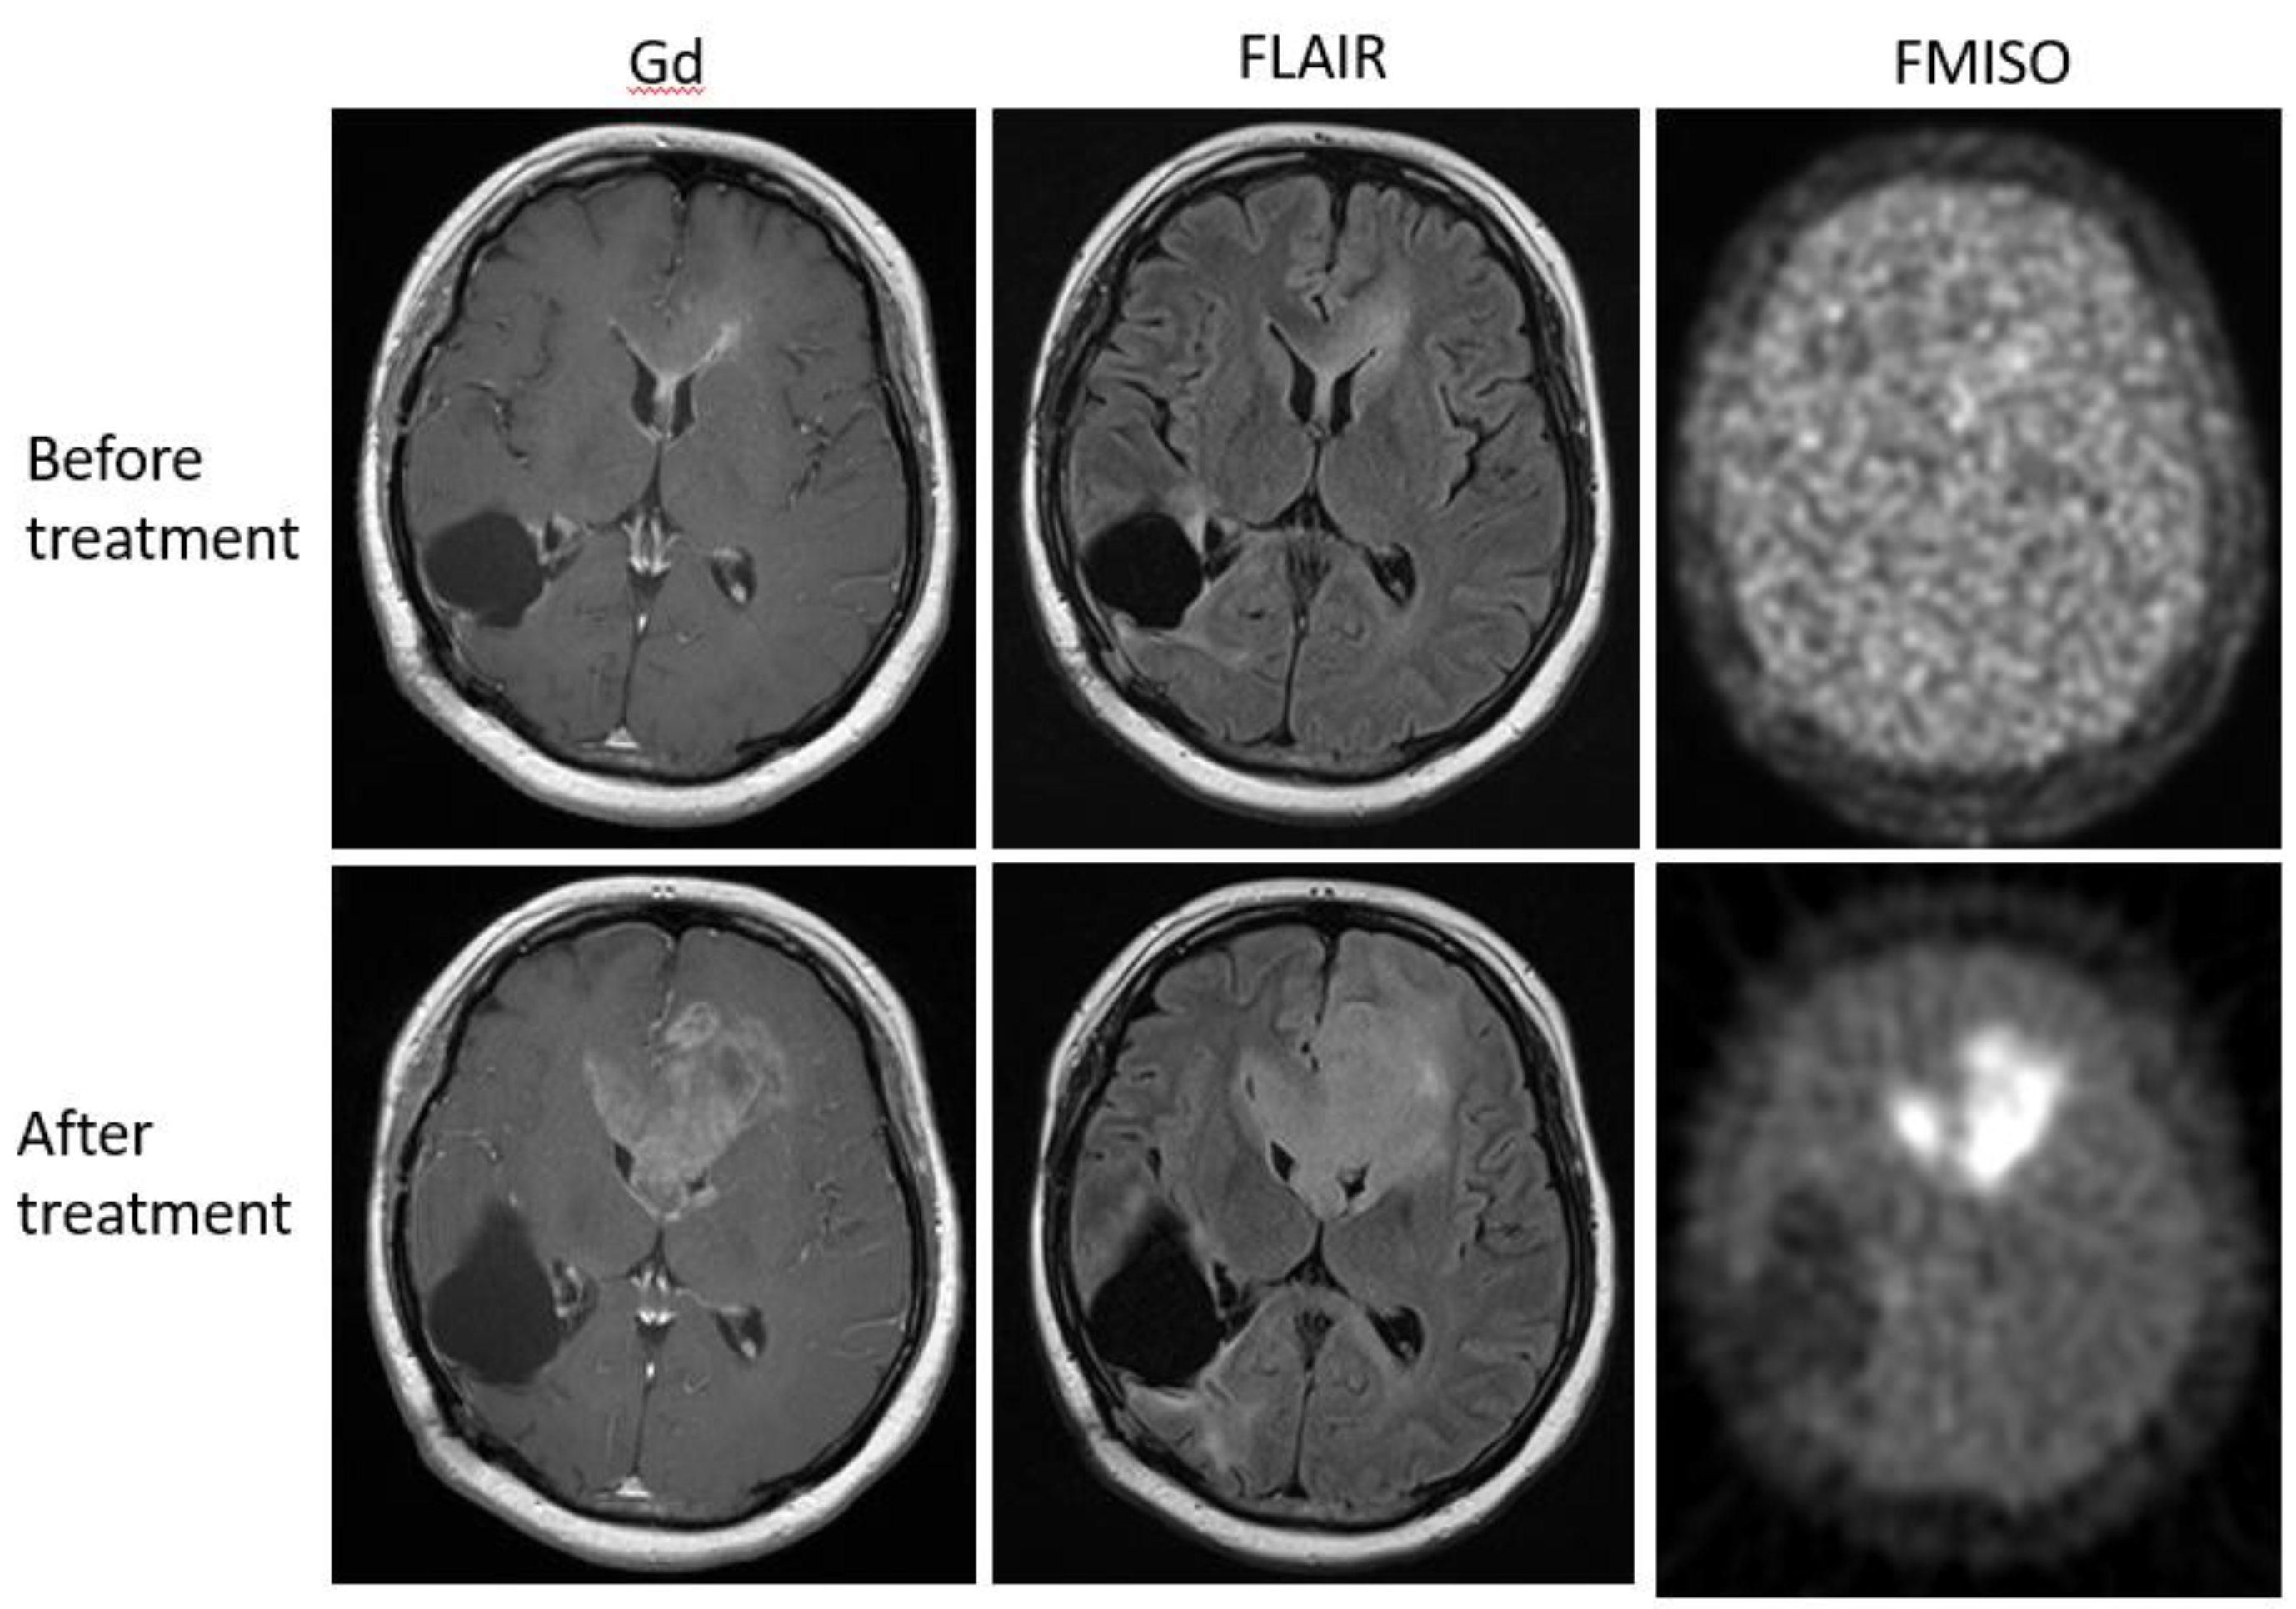

Bevacizumab is a recombinant humanized monoclonal antibody that blocks angiogenesis by inhibiting vascular endothelial growth factor A (VEGF-A) [58]. Although bevacizumab failed to prolong the overall survival of patients with primary glioblastoma [59,60], it was effective in some populations of recurrent glioma patients. In our retrospective study, we investigated whether FMISO PET has the potential to distinguish responders to bevacizumab from non-responders [61]. Eighteen patients with recurrent glioma underwent bevacizumab treatment. We compared the patients’ pre-and post-MRI and FMISO PET to classify them as (1) MRI-FMISO double responders (n = 9, Figure 5), (2) MRI-only responders (n = 5, Figure 6), and (3) non-responders (n = 4, Figure 7). There were no FMISO-only responders. The survival analysis demonstrated that the MRI-FMISO double responders had significantly longer overall survival than the other patients, whereas no significant difference was observed between the MRI-only responders and the non-responders. We thus concluded that recurrent gliomas with decreasing FMISO accumulation after short-term bevacizumab application could derive a survival benefit from the treatment.

Figure 5. A 47-year-old patient with glioblastoma showed a strong uptake of FMISO before the bevacizumab treatment (upper row), but the FMISO uptake disappeared after the treatment (lower row). This patient was considered a ‘MRI-FMISO double responder’.